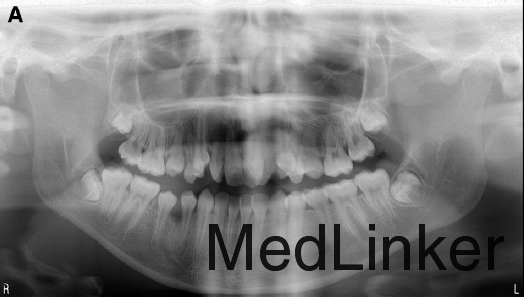

女,14岁,牙齿排列非常不整齐,微笑时牙弓特别狭窄,要求解决.小时候有鼻呼吸道的阻塞及过敏性鼻炎,可能是导致错合的病因。

直面型,上颌严重横向不调伴严重拥挤(拥挤度17mm),前牙及双侧后牙反合,下牙列重度拥挤,左侧磨牙I类,右侧磨牙II类关系,双侧尖牙II类关系。劲椎片可见其已过生长发育期